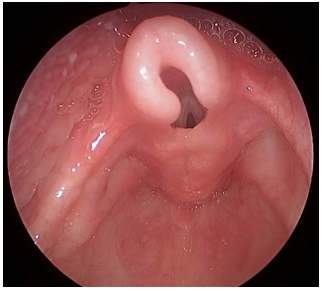

Menina, 9 anos de idade, apresenta febre há dois dias, com picos de até 38,2 °C ocorrendo duas a três vezes ao dia, associada à prostração. Nega coriza, tosse ou rouquidão. Ao exame físico, observa-se linfonodo submandibular direito aumentado, medindo cerca de 2 cm e doloroso à palpação. À oroscopia, observam-se os seguintes achados:

Enunciado 4540961-1

Com base nessas informações, o agente etiológico mais provável nessa situação é: